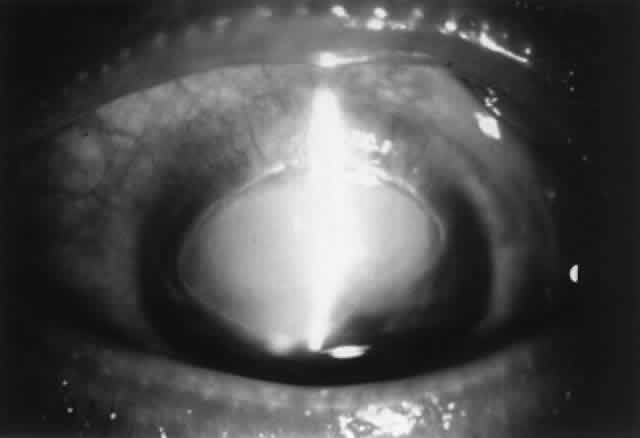

Pathogenesis

Several factors may be involved in pathogenesis. Mechanical irritation by the contact lens probably plays a role, especially lenses with thick edges, as seen in myopes. Accumulated deposits of protein, lipid, and minerals on the contact lens surface act as a source of antigens that can sensitize the conjunctiva. Chronic microtrauma by the lens and its deposits disrupts tight junctions between conjunctival epithelial cells, allowing allergens to penetrate. Damage to conjunctival epithelial cells induced by contact lenses and their deposits stimulates the production of neutrophil chemotactic factors, which play a role in the inflammatory response.83–85 Certain lens polymers (e.g., hydrogels) are more prone to accumulation of deposits. Also, larger lenses provide a greater surface area for deposits to accumulate and a greater surface area for antigens to contact the conjunctiva. Long wearing times allow a longer period of conjunctival exposure to antigen. Meibomian gland dysfunction may play a role in deposit formation and contact lens intolerance.86–88

The allergic mechanism in GPC is probably a basophil-rich delayed hypersensitivity (type IV) reaction with a possible IgE (type I) humoral component.82,89 An abnormal distribution of inflammatory cells is seen. There are mast cells in the conjunctival epithelium (not seen in normals) and increased numbers of mast cells in the substantia propria. Basophils and/or eosinophils, not usually seen in normal conjunctiva, may be found in increased numbers in both the epithelium and substantia propria.82 Although tear histamine levels are normal, tear immunoglobulins are increased.90,91 As with vernal, eosinophil major basic protein, which stimulates mast cell degranulation and possesses cytotoxic effects that may enhance the conjunctival inflammatory reaction, is found in increased amounts in the conjunctiva (but not in tears as in vernal) and undoubtedly plays a role.64 Tear tryptase levels in patients with GPC, a measure of mast cell degranulation, may provide an early marker for this disease.92

Treatment